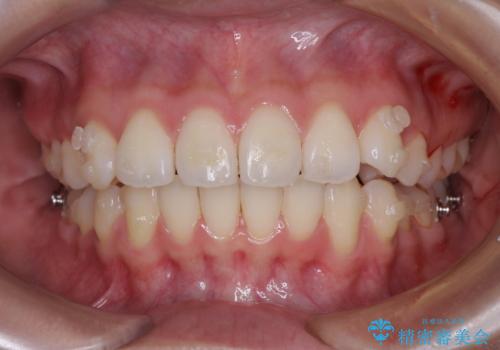

前歯のデコボコを解消 インビザラインの矯正治療

- 前歯のデコボコを治したいとのことで来院された患者様です。

上下顎ともに歯列全体の後方移動とIPR(歯と歯の間を削る)によってデコボコが解消するように設計し、インビザラインにより治療を行うこととしました。